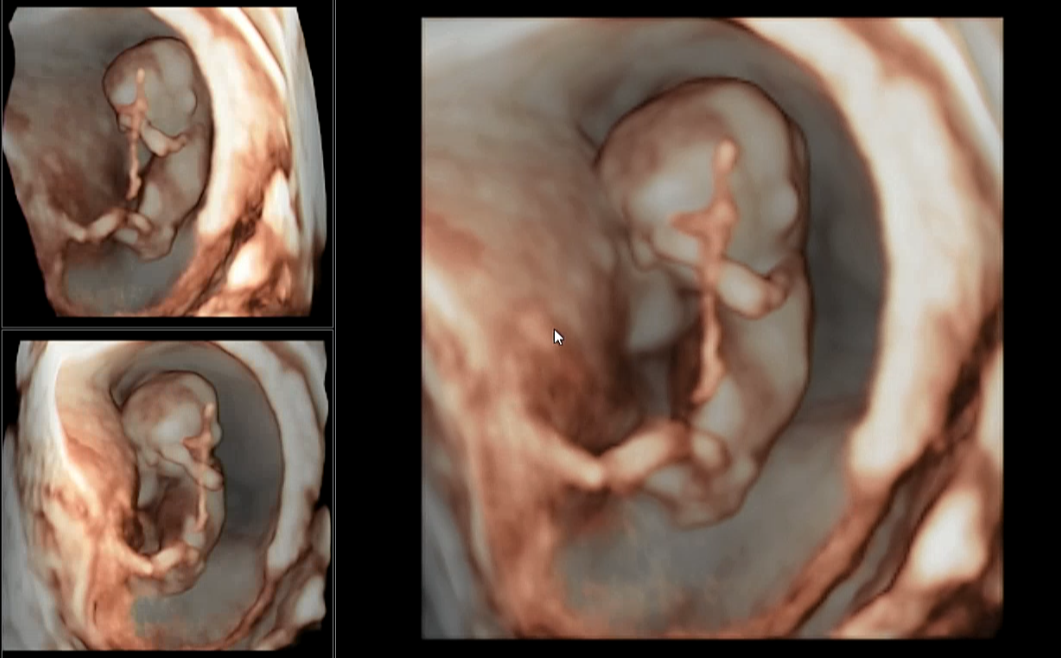

저번에는 젤리곰의 형태를 하고 있었는데, 이제 얼추 사람의 형태를 보이고 있어요.

입체 초음파도 보고 심박수도 173 bpm으로 확인!

다행히 심박수가 떨어졌어요. 정상 범위로 돌아왔답니다.

목투명대도 1.14센티로 정상이었어요.